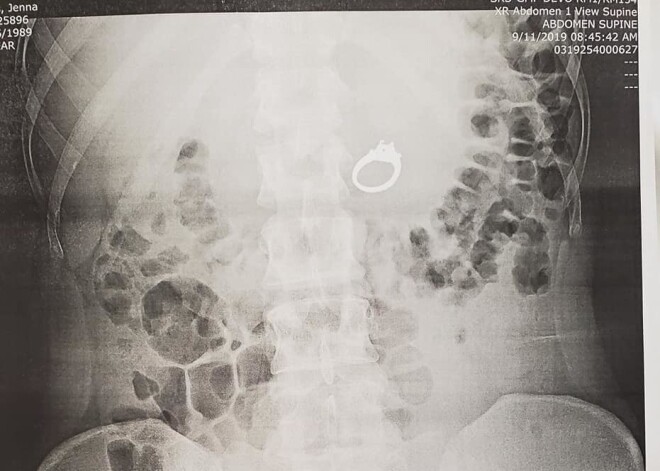

Pēc notikušā Dženna devās pie ārsta, kur tika veikti rentgenuzņēmumi. Attēlos skaidri un gaiši redzams - saderināšanās gredzens patiešām atrodas sievietes vēderā.